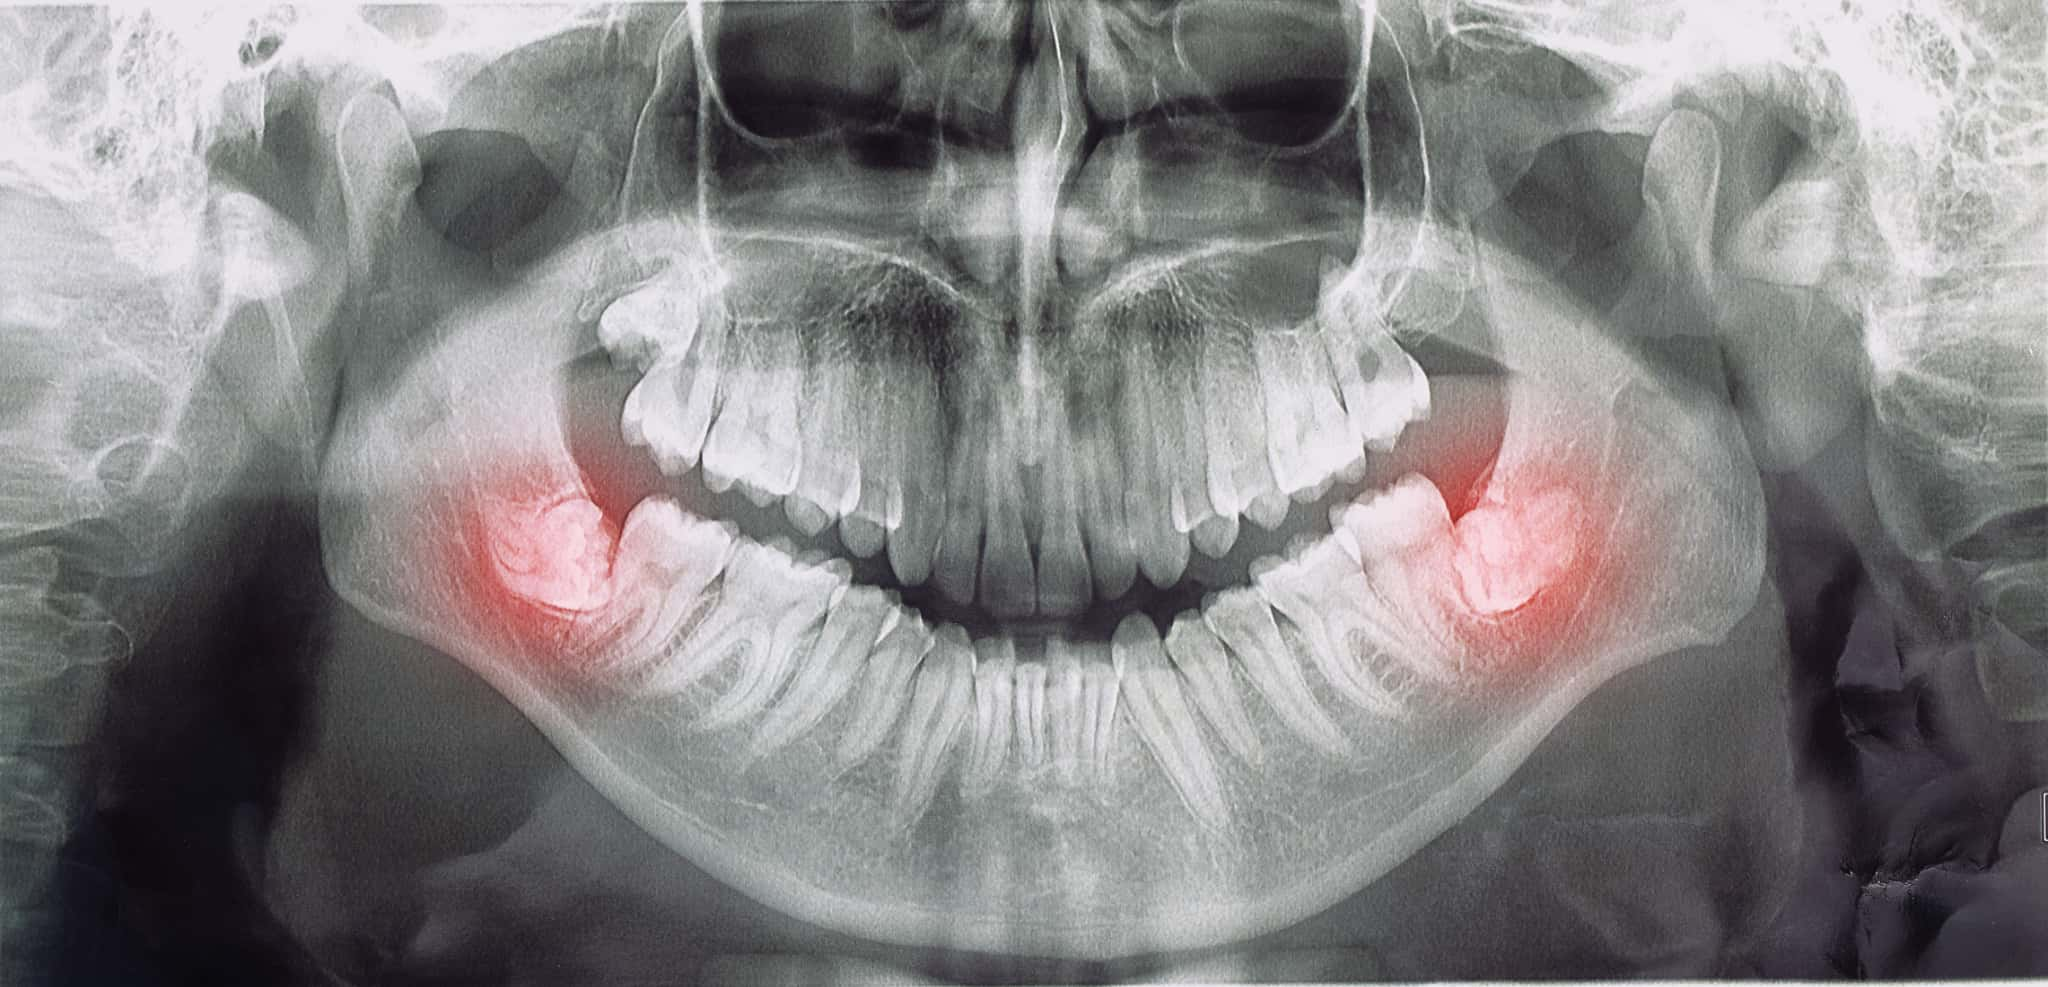

親知らずは最後に生えてくる永久歯で、横向きに生えるケースも少なくありません。横向きに生えた親知らずは、歯並びや噛み合わせに悪影響を与えることがあるため、抜歯が推奨されるケースも多いです。

横向きに生えている親知らずは、抜歯が必要とされるケースが多いです。なぜなら、横向きに生えた歯は歯ぐきの中に埋まったままだったり、一部だけ顔を出していたりすることが多く、周囲の歯や歯ぐきに悪影響を与えることがあるからです。

虫歯や歯周病を繰り返したり、痛みや腫れがあったりする場合は、抜歯を検討することが多いでしょう。

親知らずが横向きに生えた場合の抜歯方法

事前診察と検査

まずは、歯科医師による診察とレントゲン撮影、場合によってはCT撮影を行い、親知らずの位置や根の形、神経との距離を詳しく確認します。